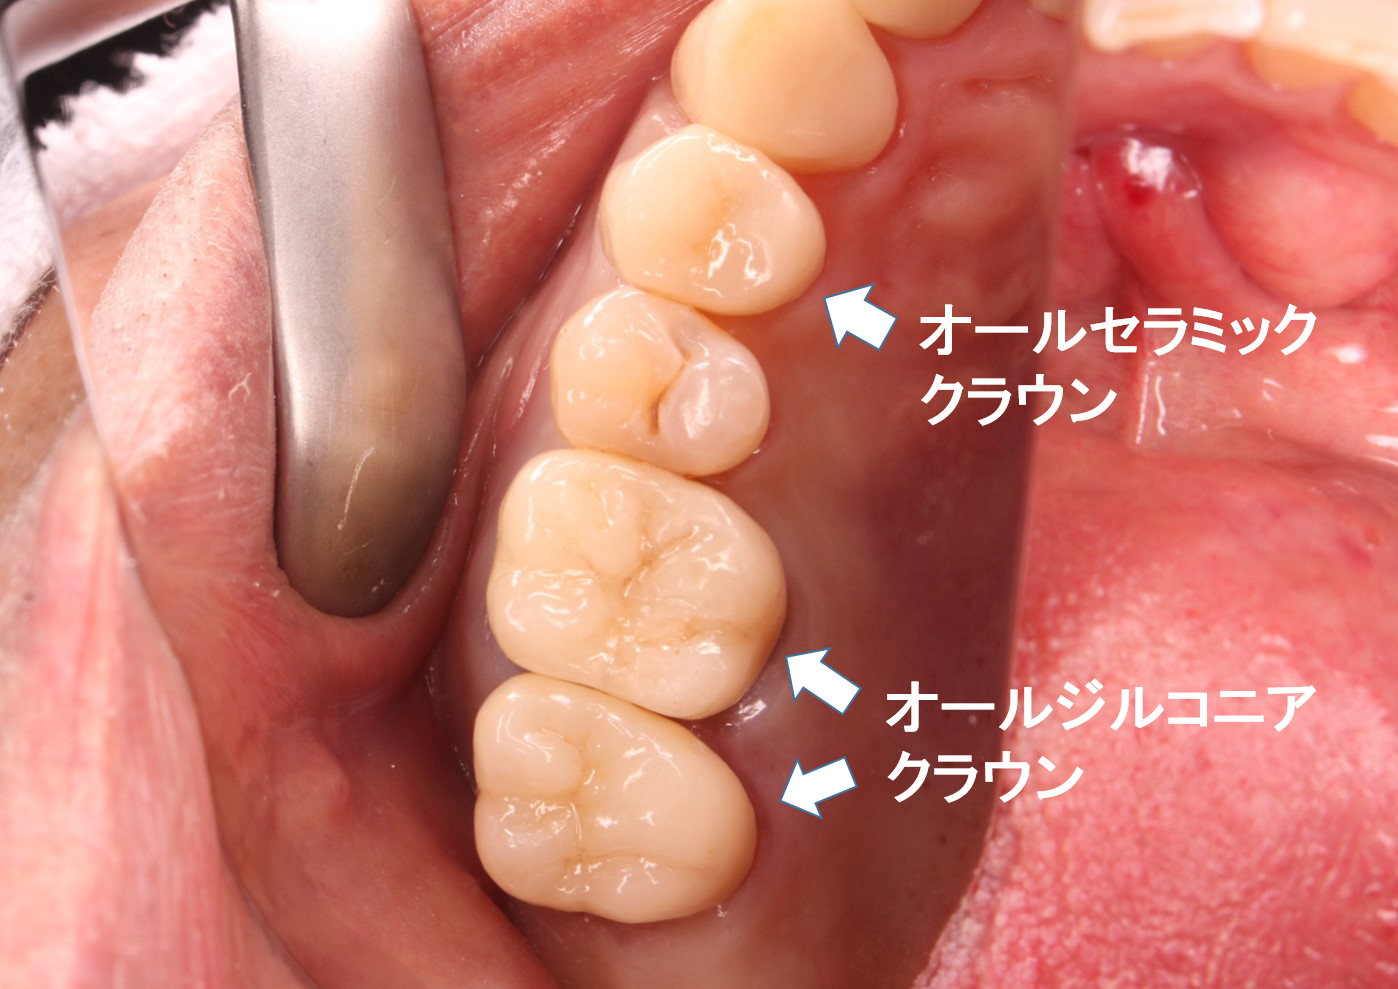

審美治療 セラミックジルコニア

こんにちは。 南館歯科クリニックの木村です。 上の奥歯の審美治療のケースをご紹介します。 治療前 治療後 もともと銀歯治療がされていて、白くしたいという主訴で来院されました。 除去してみると、やはり2…